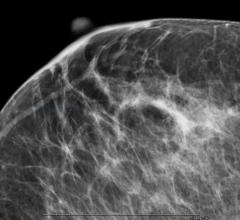

The women’s health channel includes news, videos, podcasts and other content related to technology used to detect and treat breast cancer and cervical cancer, including mammography, breast magnetic resonance imaging (MRI), automated breast ultrasound (ABUS), breast ultrasound, breast biopsy and breast radiation therapy.

Despite decades of progress in breast imaging, one challenge continues to test even the most skilled radiologists ...

Throughout the years, imaging technologies have continued to improve for the screening and detection of cancer in the ...

Criticism and confusion notwithstanding regarding the appropriateness of X-ray mammography as the gold standard in ...